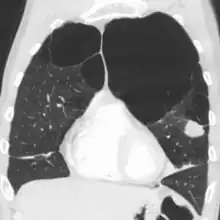

- A severe case of bullous emphysema

- Axial CT image of the lung of a person with end-stage bullous emphysema